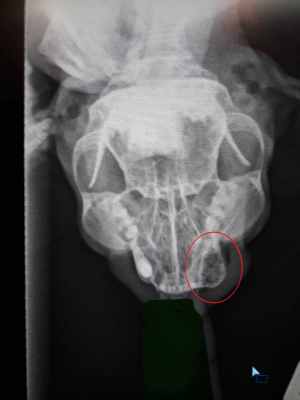

Самое плохое. Под вопросом вялотекущие. Под вопросом онкология, но кость на рентгене не затронута.

На рентгене обвела зону воспаления красным. Очень просим о помощи, одна я кота не вытяну. Девочки, может кто знает, куда, к кому можно стукнуться, попросить сделать пост на поиск финпомощи в соцсетях?